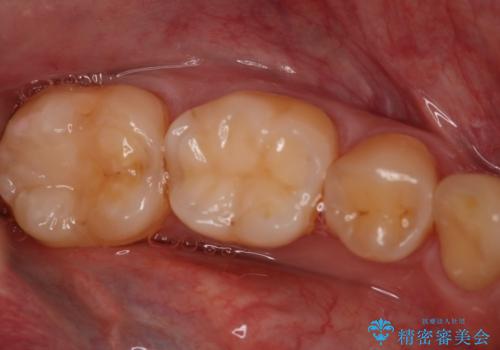

- 左下7番のCR劣化を自費治療にて希望された患者様です。

切削量を考慮してセラミックインレーでの治療を選択しました。

CR直下と隣接面にう蝕が進行していたので、除去した上で形成、印象しています。